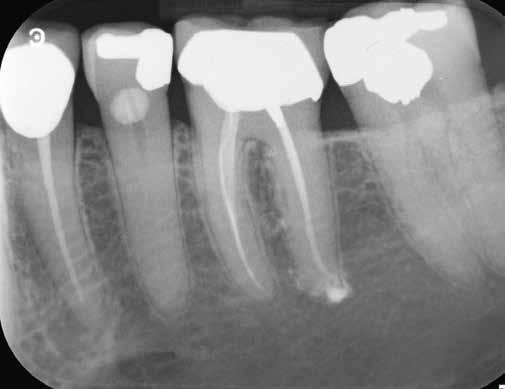

1. a-n. ábrák: Preoperatív CBCT-felvétel a bal alsó 6-os (3.6) fogról. Az axialis (a), coronalis (b) és sagittalis (c) nézeteken a mezialis és distalis gyökerek apicalis harmada körül sugáráteresztő zóna és ép buccalis corticalis csont látható. Egy olyan sablont terveztünk, amely jelezte a csontablak határait az apicalis terület pontos elérése érdekében (d). A mikrosebészeti bevatkozás során a sablont a helyére illesztettük (e), a csontablak határait megjelöltük (f) egy Piezotome CUBE LED kézi-darabba fogott fűrésszel, majd kivágtuk és eltávolítottuk (g és h) az apicalis területhez történő hozzáférés, illetve a mezialis és distalis gyökerek rezekciójának, retrográd preparációjának és retrográd gyökértömésének elvégzése érdekében (i). Végezetül a csontablakot visszaillesztettük és kollagén szivaccsal stabilizáltuk (j). A műtét után közvetlenül készített röntgenfelvétel a 3.6-os fogról (k). A kétéves kontroll során készített CBCT-felvétel: axialis (l), coronalis (m) és sagittalis (n) nézetek.

Egy 63 éves páciens korábban már kezelt bal alsó első nagyőrlőfogából (3.6) eredő mérsékelt fájdalom miatt kereste fel rendelőnket. A kórtörténetében panasza szempontjából releváns információ nem szerepelt. Az elkészült CBCT-felvételen a korábbi kezelések során észre nem vett, jelenleg feltáratlan meziobuccalis csatornát, valamint a mezialis és distalis gyökerek körül kialakult periapicalis elváltozást, és ezt a léziót borító intakt buccalis corticalis csontlemezt láttunk.

Klinikai vizsgálat során vertikális kopogtatási érzékenységet jelzett. A fog körül mérhető szondázási mélység és a fogmobilitás fiziológiás volt. A CBCT-felvételen nem észleltünk a csontos regeneráció megindulására utaló jeleket (1. a–c. ábrák). A korábban gyökérkezelt, gyökértömött és revideált 3.6-os fog esetében az alábbi diagnózis került felállításra: periodontitis periapicalis symptomatica. A panaszokat okozó fog további ellátása során navigált endodonciai mikrosebészetet kívántunk alkalmazni. Az alsó állcsontról intraorális szkent (TRIOS, 3Shape) készítettünk, és a felszíni topográfiát tartalmazó STL fájlt, valamint a CBCT-felvétel készítése során nyert DICOM fájlokat a Blue Sky Bio szoftver segítségével egyesítettük. A sebészi sablon megtervezésére az így kapott háromdimenziós képet használtuk. A sablon kialakítása során arra törekedtünk, hogy a sablon egyértelműen meghatározza a gyökércsúcsi terület eléréséhez szükséges csontablak határait (1. d. ábra)

A beavatkozás során helyi érzéstelenítésben teljes vastagságú mucoperiostealis lebenyt képeztünk, és a sablon segítségével bejelöltük a preparálandó csontablak határait. Az ablak széleinek megfelelően Piezotome CUBE LED kézi-darabbal (ACTEON) a kortikális teljes vastagságában vágást ejtettünk, majd az így kapott csontlemezt (ablakot) eltávolítottuk (1. e–h. ábra), és ezt követően steril fiziológiás sóoldatba helyeztük. A rezekció elvégzését követően (1. i. ábra) a mezialis csatornákat ultrahangos eszközök segítségével (NSK) retrográd irányból preparáltuk, majd az így kialakított mélyedésbe retrográd gyökértömést készítettünk. A tömés anyagául az EndoSequence BC RRM Fast Set Putty-t (Brasseler) választottuk. A tömés elkészítését követően a csontablakot visszaillesztettük, és a stabilizálása érdekében a vágásoknak megfelelően kialakult résekbe kollagén szivacsokat (Collagen Tape, Zimmer Biomet) helyeztünk (1. j-k. ábra). A lebenyt 6/0-s Prolene varratokkal (Corpaul) rögzítettük.

A kétéves kontroll során elvégzett klinikai és radiológiai vizsgálat (CBCT-felvétel) a periapicalis elváltozások megszűnését és a corticalis csontállomány tünet- és szövődménymentes gyógyulását